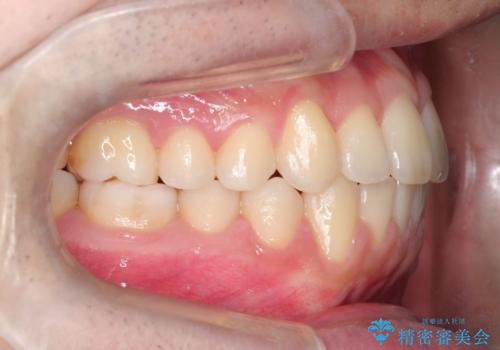

【クリア装置】前歯の凸凹を綺麗にしたい

- 前歯の凸凹を主訴に来院されました。

マウスピース矯正も適応でしたが、ワイヤー矯正を希望され治療を行なっております

治療期間も短く大変満足していただきました。